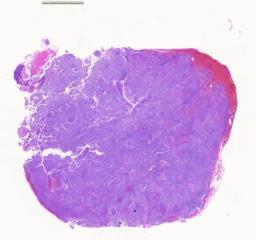

临床资料: 病人信息,女,72岁,取材部位:左颈部淋巴结,临床病史:患者1周无意间发现左颈部肿块,无压痛,无发热、头痛、咳哦、咳痰、胸痛、胸闷,无尿频、尿痛、盗汗等不适(送至我院门诊)彩超提示:左侧颈部多发肿大淋巴结,建议住院。发病以来,精神状态、饮食一般,睡眠状况上常,小便正常,大便不规律,体力不降,体重无明显变化。特殊影像学及实验室检查:胸腹部CT提示:双侧颈部、颈后、锁骨上窝、颈根部、纵隔、双侧胶窝、心膈角区、肝胃间隙、腹膜后、腹岔腔、双侧髂血管旁、双侧腹股沟区多发小及肿大淋巴结,考虑淋巴瘤可能性大。脾大。其他实验室检查:肿瘤标志物(CA199):50.17U/L(0-35)巨细胞病毒DNA检测:<5X10copies/ml(<5X102)EB病毒DNA检测:<5.00E+copies/ml(≤5.00E+2)乳酸脱氢酶(LDH):824U/L(90-245)B2微球蛋白:6.84mg/L(1.3-3.0)血沉:57mm/h(0-30)